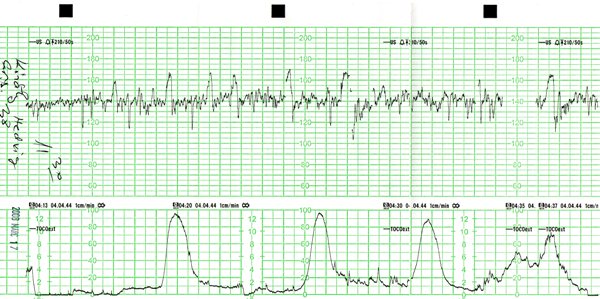

Jim, szívesen megcsináltam volna kért átlagolásokat stbstb, de látom Mniki már be is előzőtt

de télleg érdekes lesz majd néhány ilyen adat... aztán elemezgethetünk össze-vissza

és tessék már meggyógyulni végre!!! nagyon rossz ezt olvasni!!! és télleg nem marad erőd a szülésre!!! pedig ha a lányok mondják, akkor én elhiszem hogy ezek a görbék nem kicsik... lehet hogy Te leszel a köv?

holnap megyünk ahoz a dokihoz akivel szülünk, és állítólag lesz ctg.

nekem olyan még sosem volt. kivi vagyok